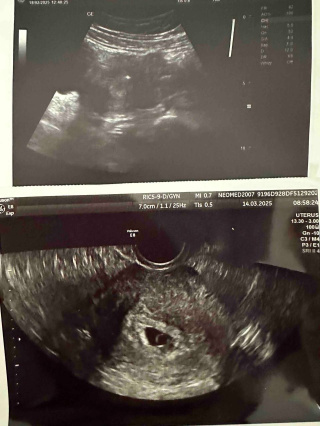

До медичного центру звернулась молода жінка після тривалих спроб завагітніти. Протягом трьох років природна вагітність не наставала. Під час обстеження у 29 років було виявлено первинне безпліддя, низький оваріальний резерв та ендометріоїдні кісти. На УЗД лікар побачив лише по два антральні фолікули в кожному яєчнику.

• Стимуляція та пункція: вдалося отримати 4 яйцеклітини.

• Запліднення: у лабораторії сформувалось 2 якісних ембріони.

• Перенесення: обидва ембріони були перенесені у порожнину матки.

• Результат: вагітність настала одразу і розвивалась двійнею.

Вагітність проходила без ускладнень. Пологи відбулися шляхом кесаревого розтину, і на світ з’явилися двоє здорових дітей. Це доводить, що навіть при таких діагнозах, як низький оваріальний резерв чи ендометріоз, сучасні методи допоміжних репродуктивних технологій дають результат.